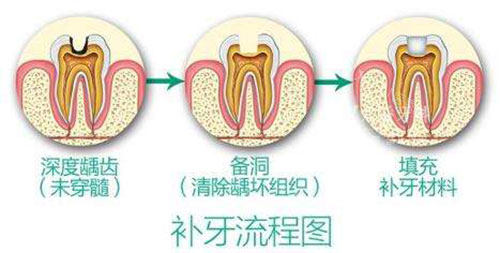

没等多久,就轮到我看牙了。给我看牙的是一位姓张的医生,张医生特别亲切,先是让我躺在牙椅上,然后用可靠的仪器给我的牙齿做了详细的检查。他一边检查一边跟我解释,说我的蛀牙还不算特别重度,只要把龋坏的部分清理干净,再补上就可以了。他还跟我说了补牙的材料有好几种,让我可以根据自己的需求和经济情况来选择。

我选了一种中等价位的补牙材料,张医生就开始给我补牙了。整个过程中,他的动作特别轻柔,还时不时问我疼不疼。清理龋坏部分的时候,其实有点酸酸的,但还能忍受。补完牙后,张医生还教了我正确的刷牙方法和日常护牙的小知识,让我以后一定要好好保护牙齿。